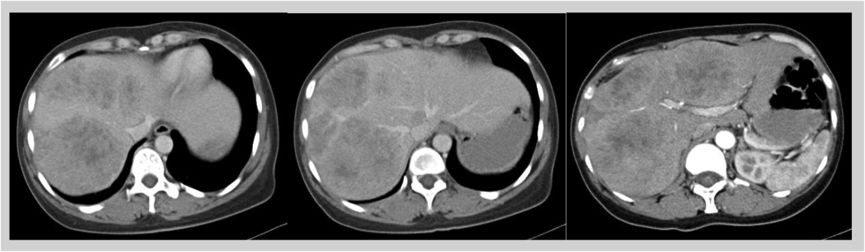

2017-11-03 腹部CT增强:肝内见多发团块高低密度混杂影,增强后动脉期可见边缘强化伴内部网格状强化。乙状结肠近直肠肠腔狭窄,局部管壁增厚,增强后呈渐进强化,盆周多个肿大淋巴结。

1. 该患者诊断为结肠癌伴多发性肝转移,肝脏MR增强示肝右叶及左内叶可见多发团状异常信号影,考虑为转移瘤。较大者位于V及VI段,大小约13*7cm,肿瘤病灶大,负担重,转移瘤肝转移灶初始不可切除

2. 考虑患者情况,首先选择FOLFIRI+西妥昔单抗(爱必妥)方案进行转化治疗,每2周一次,治疗8周期后,转化治疗疗效显著,肝转移灶部分缓解,肝脏转移灶转化治疗后由原先的不可切除变为可切除